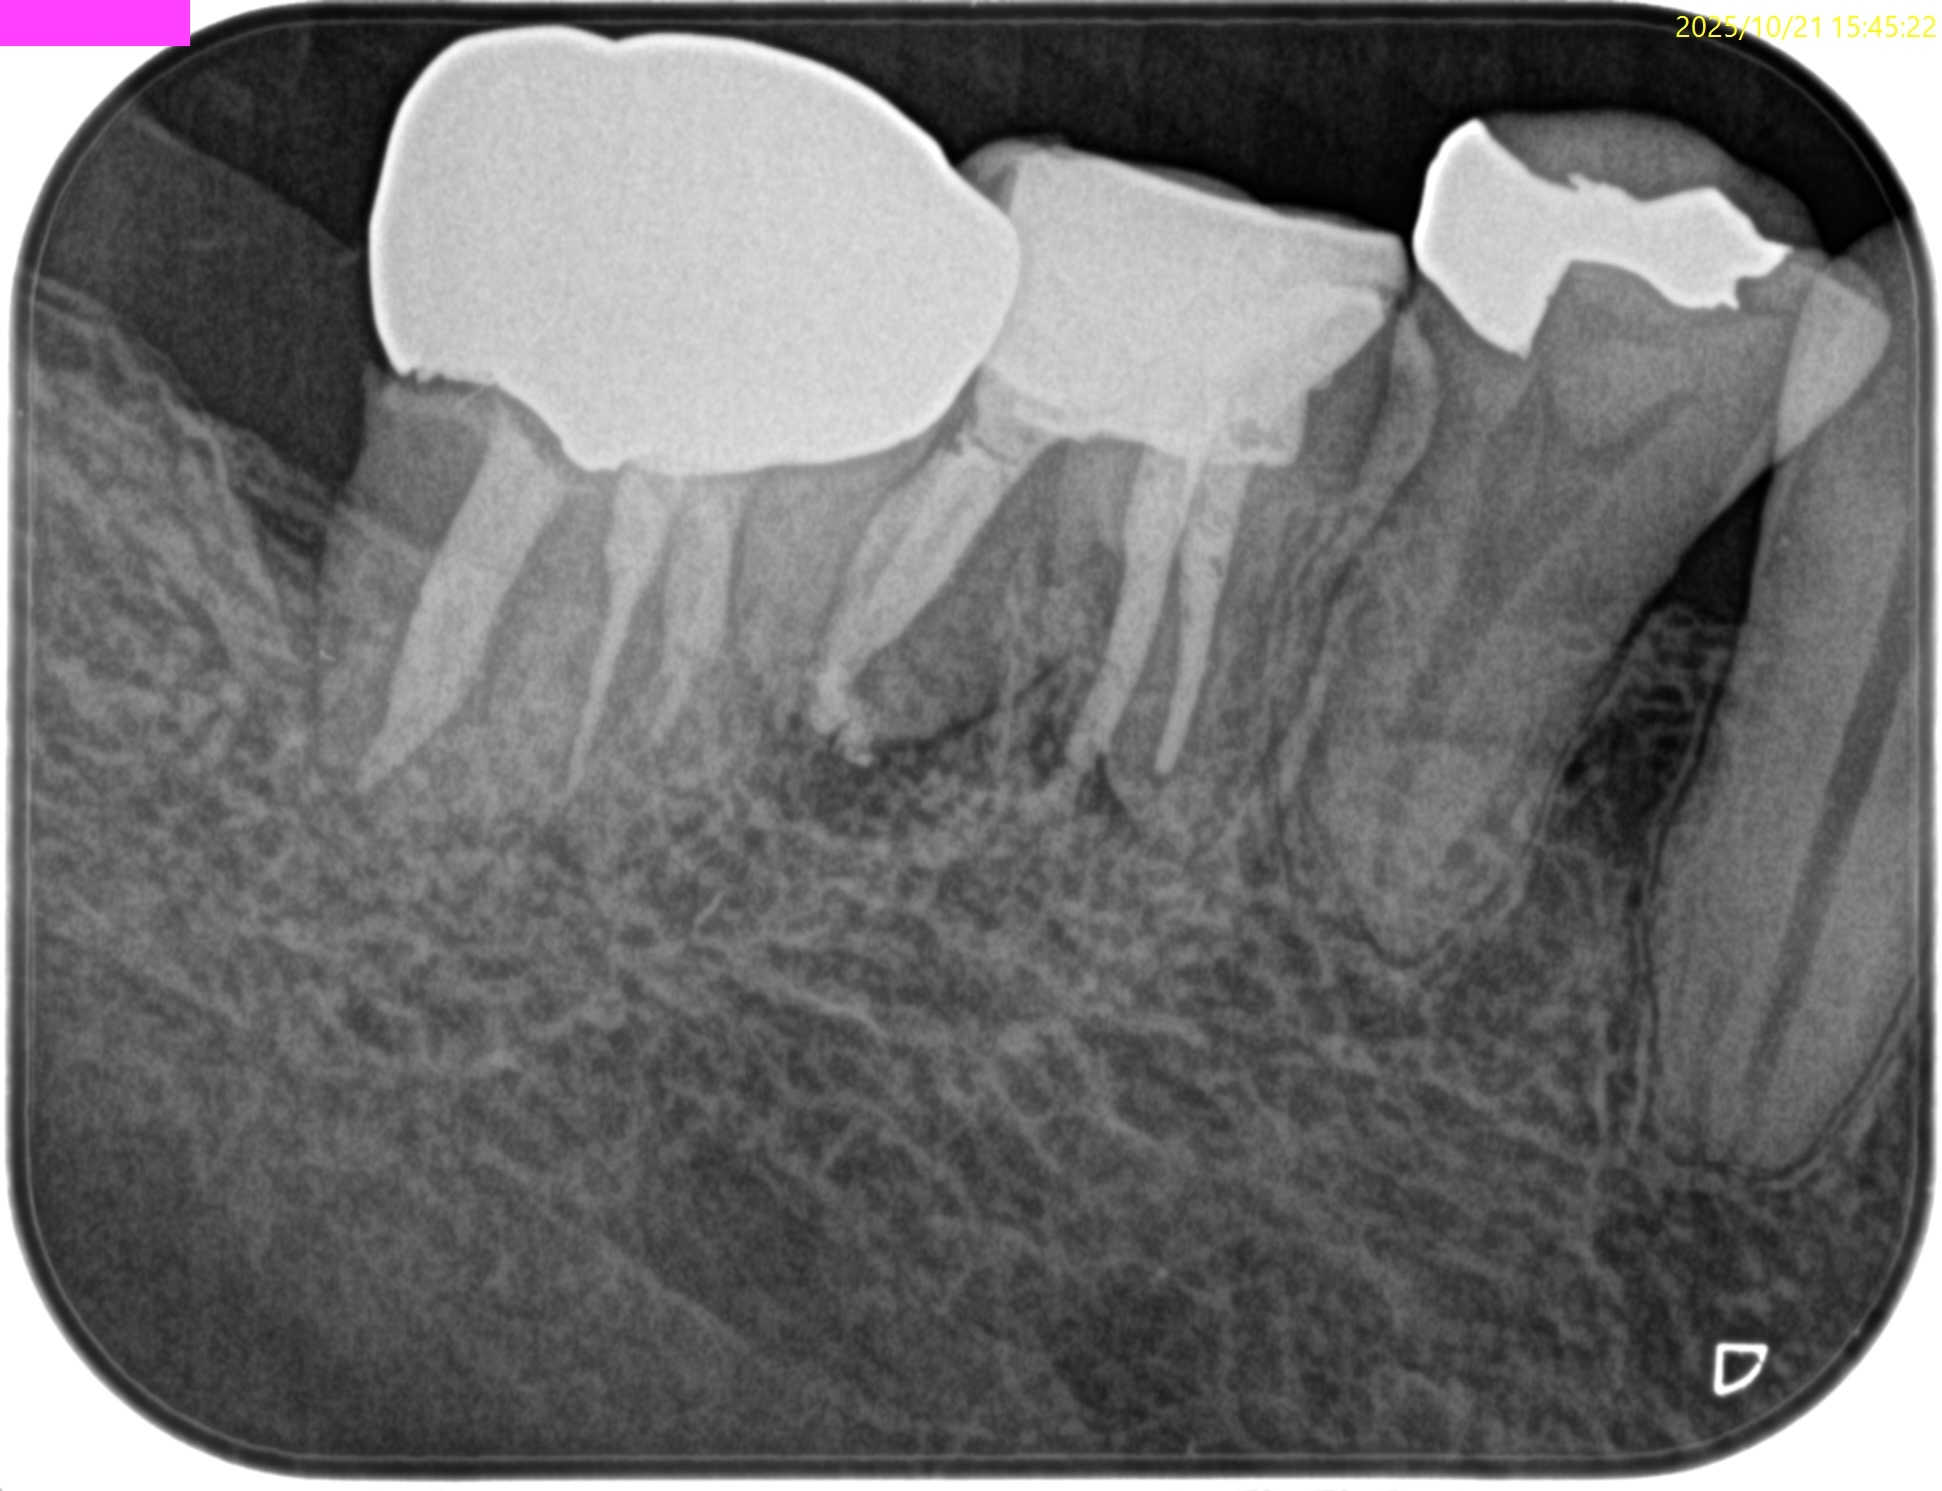

術後にPA, CBCTを撮影した。

#30

MB

ML

D

かかりつけ医にはプロビジョナルレストレーションの装着を依頼した。

次回は半年後である。